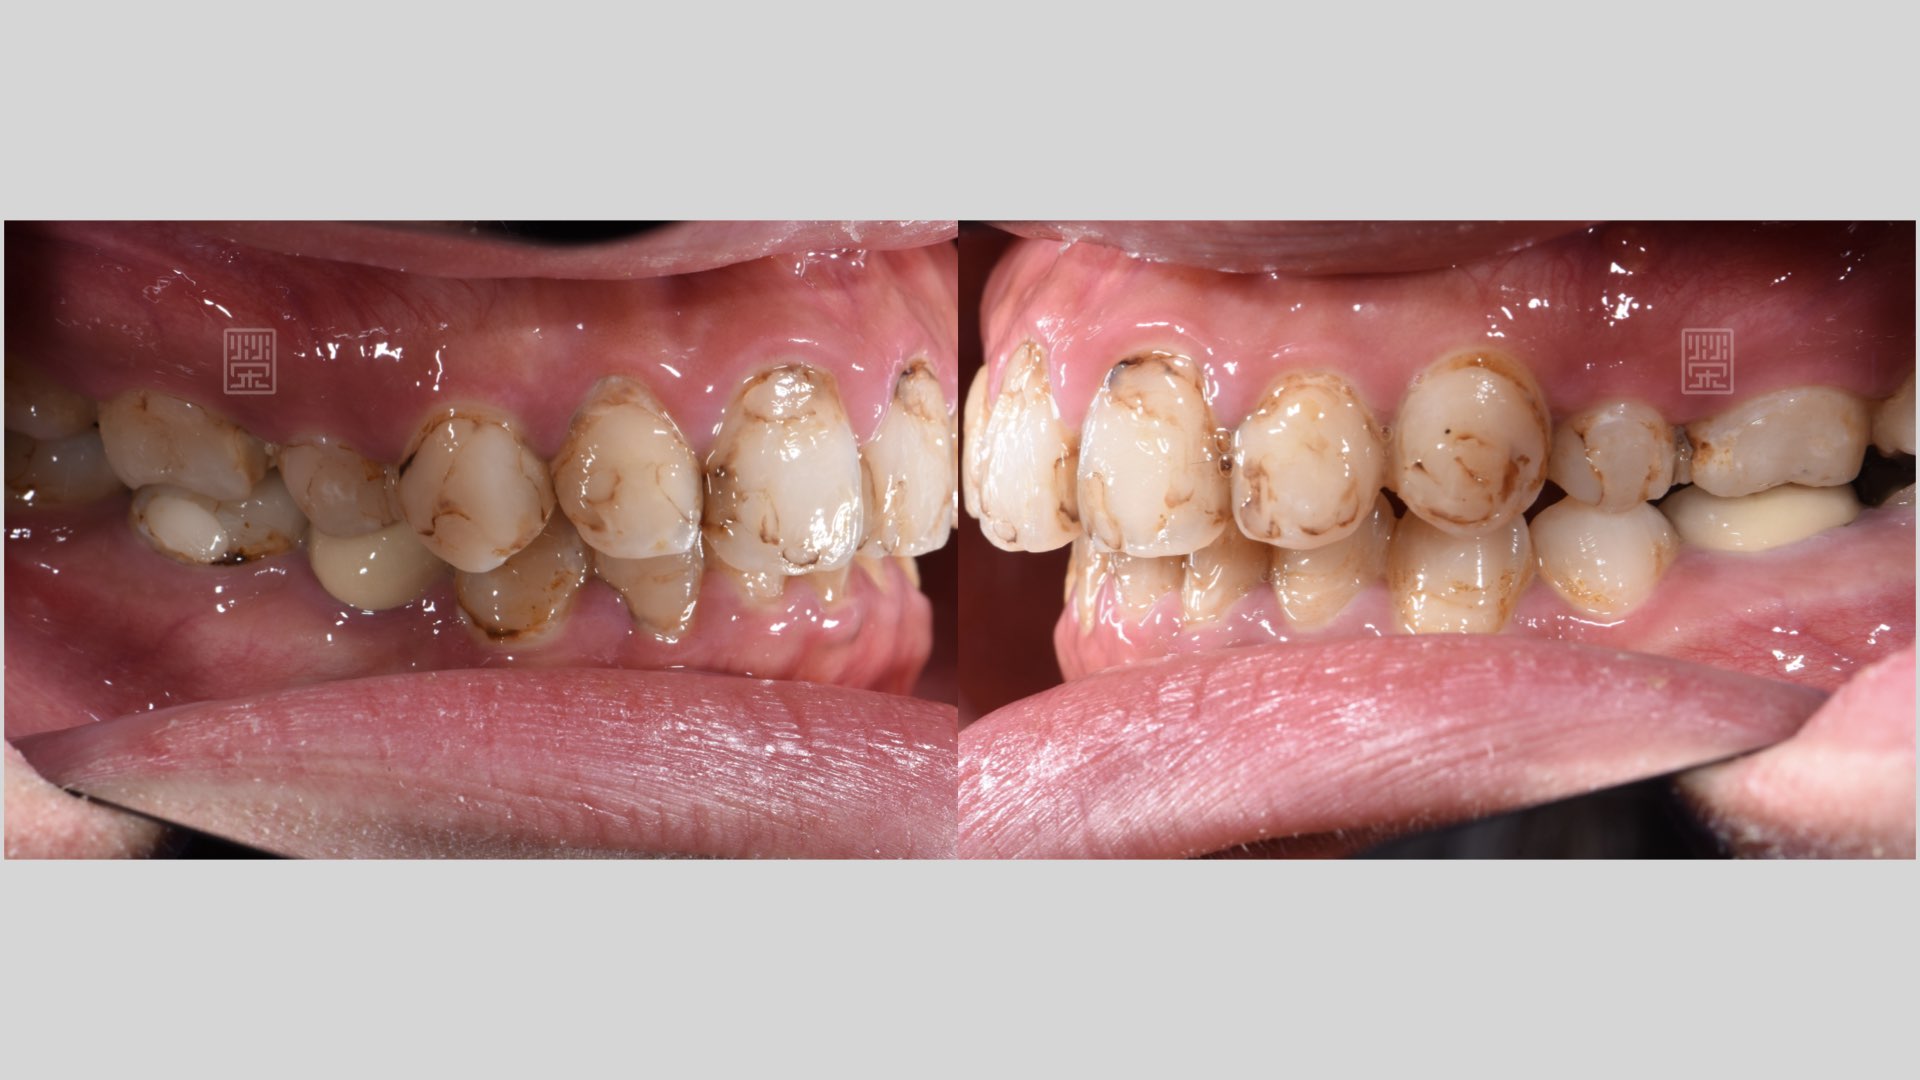

陳小姐覺得自己的牙齒黃、比較暗沈,加上小時候補牙的痕跡明顯,多年來,牙齒多次樹脂填補治療,顏色都不均勻,到榮醫師的門診檢查後發現,過去多次的蛀牙治療,許多牙位都損傷嚴重。

雖然一開始陳小姐是希望改善門牙外觀,但口腔裡每個位置有不同的角色,有好的後牙臼齒支撐才能夠維持長期門牙的美觀,所以榮醫師建議利用全瓷貼片與全瓷嵌體全口重新治療。

後牙多次蛀牙填補

門齒多次蛀牙填補